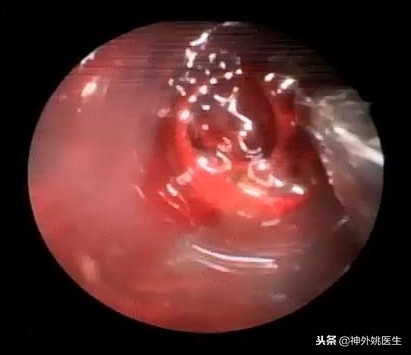

术中所见:(图2-4)

图3 球囊引导通道进入血肿。

图3 神经内镜下经通道内清除血肿。

图4 清除脑室内血肿,显露脑室壁及脉络丛。